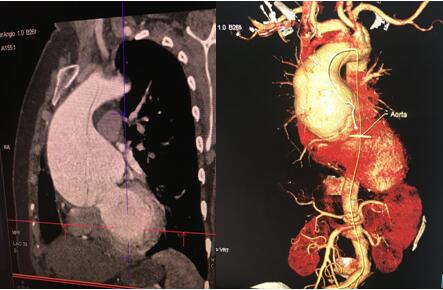

術前CTA影像:升主動脈擴張明顯,最大直徑10cm

術前升主動脈瘤樣擴張和術后人工血管置換后